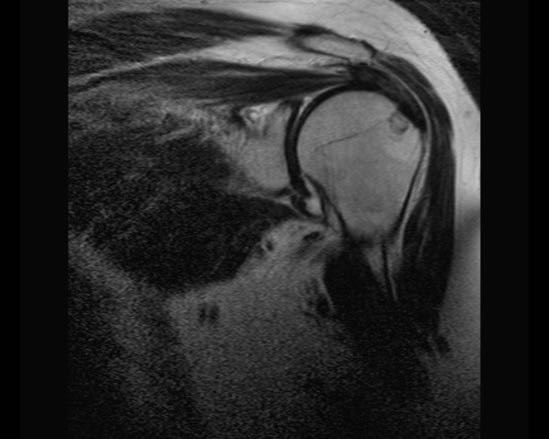

Rách toàn bộ chiều dày hoàn toàn

Nhấp vào hình ảnh để phóng to, sau đó cuộn qua các lát cắt.

Có hình ảnh rách toàn bộ chiều dày gân cơ trên gai kèm co rút và teo cơ.

Lưu ý các dải mỡ trong cơ tròn bé, cơ trên gai và cơ dưới gai.